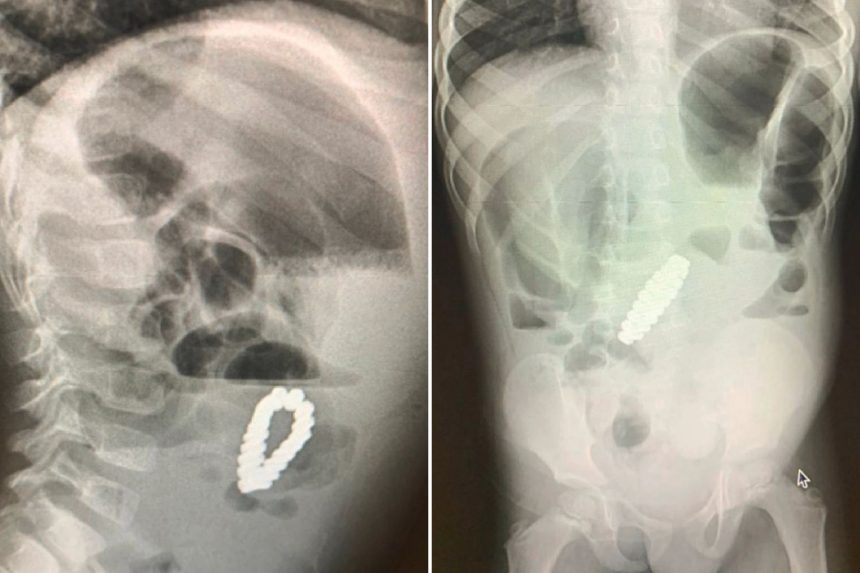

Пет дена по процедурата, лекарите направиле повторен ултразвук и откриле нараквица во стомакот на детето. Малото момче имало итна лапаротомија за да се отстрани предметот – за кој се покажало дека е нараквица составена од 18 магнетни зрнца во хексагонална форма. Нараквицата му ги попречувала цревата, како и ископала четири мали дупки во нив, кои лекарите можеле да ги поправат.